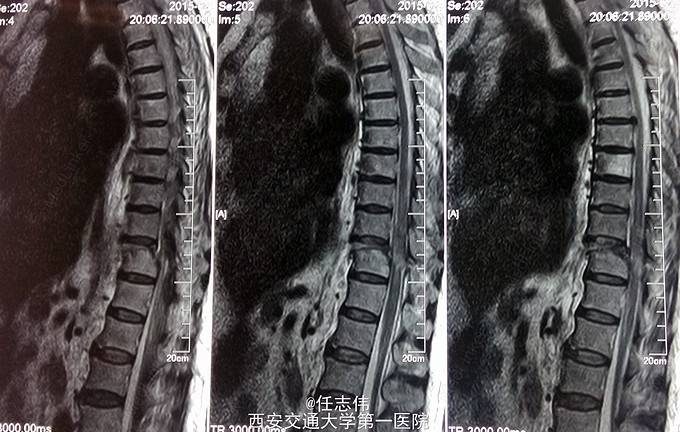

患者女性,60岁,车祸伤致双下肢感觉活动不能8h入院。 8小时前坐农用车时,被横杆撞倒腰部,摔下后感觉胸背部疼痛,双下肢活动不能,伴有短暂昏迷病史。遂来我院就诊。

诊断:1.胸11椎体骨折伴截瘫(Frankel A级)2.闭合性胸部损伤,肺挫伤,多发肋骨骨折,双侧胸腔积液 处理:1.急诊入院告病危,心电血氧监护;2.予以甲强龙冲击治疗;3.次日复查胸部CT,查看肺部损伤情况及胸腔积液,后予以右侧放置闭式引流。患者氧合不稳定,2日后复查胸片胸腔积液减少,予以行后路减压内固定融合术。 手术:术中见局部软组织损伤严重,胸11-12棘上、棘间韧带断裂,胸10、11、12双侧关节突有骨折移位,胸11椎板骨折,胸11左侧不能置入椎弓根螺钉,遂行单纯固定。脊髓局部挫伤明显,并有硬膜破损,予以处理。

术后患者逐渐病情平稳,拔出闭式引流。伤口愈合好。 查体双下肢深感觉有恢复,但肌力仍0级,巴氏征阳性。 1.在没有CT检查时,此骨折容易漏诊,需要注意询问病史,完善检查,尤其是无神经损伤表现者。 2.此患者固定范围应该扩大到腰1吗?还是至胸12就可以了,病椎大家一般都固定吗? 3.对于此例患者大家都急诊手术吗?还是要先处理肺部情况。